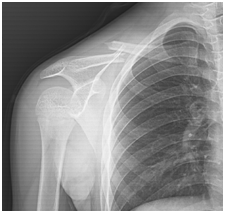

受伤后孩子诉肩膀疼痛,患肢拒动,按压锁骨疼痛明显

1.儿童因为骨头会生长塑形,所以骨头不需要对的严丝合缝,锁骨骨折只需要骨折分离不明显,骨折断 端 短缩重叠矫正即可,后期一般会恢复很好,1-2年后患儿发育塑形后会恢复原样的